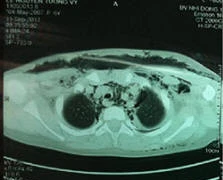

(Kiến Thức) - Khoa Tai Mũi Họng, Bệnh viện Nhi Đồng 1 TP.HCM vừa điều trị thành công một trường hợp bệnh hiếm gặp viêm mạc hoại tử.